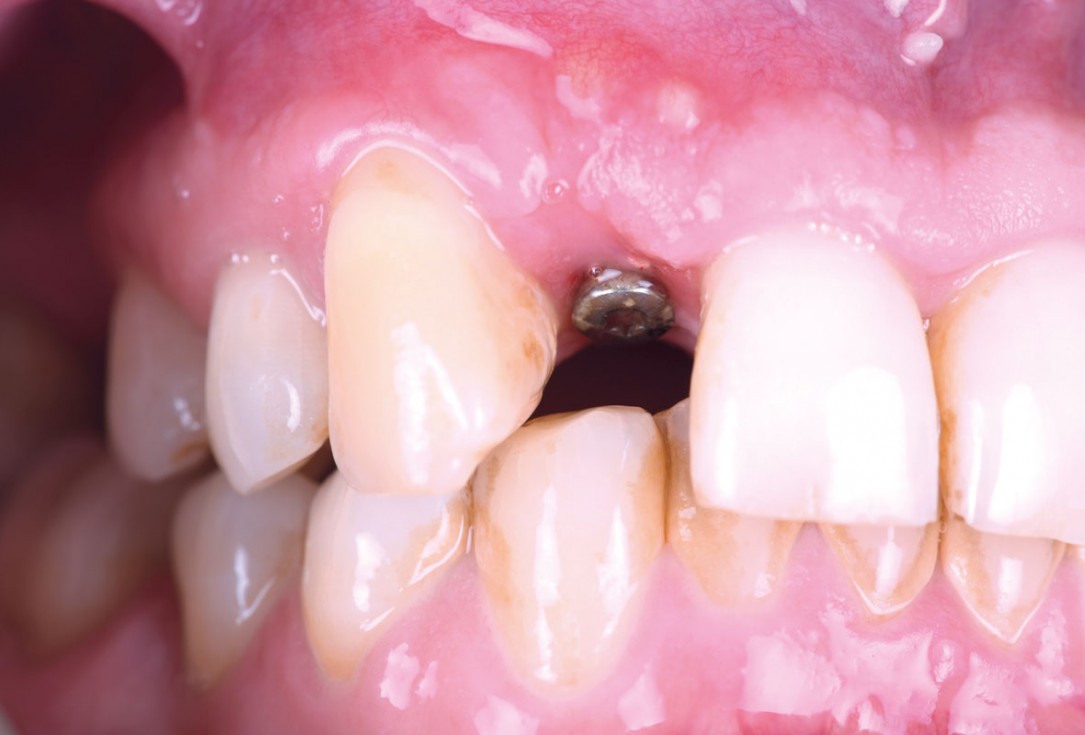

01/13 - The patient presented with a terminal fracture of the crown tooth number 12

03/13 - Root condition, gingival zenith higher than the 11, intact distal papilla and some recession in mesial papilla